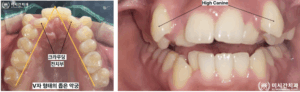

특히 상악이 지나치게 좁아지면서

악궁이 V자 형태로 형성된 경우에는

치아가 제자리를 잡지 못하고 회전하거나

송곳니가 기존보다 높은 위치로

맹출하는 상황이 발생하며

교정을 진행하신 환자분의 케이스는

상악은 매우 좁고 V자형으로

수축된 악궁 형태를 보였으며

High Canine이 두드러져

치아 배열의 불안정성이 뚜렷했습니다.

반면 하악은 전치부 총생이 있었으나

치열 폭과 악궁 형태가

비교적 유지되어 있어

비발치로도 교정이 가능하다고

판단하였습니다.

치료 과정에서는 상악은 공간부족으로 인해

위쪽으로 맹출된 송곳니를

자연스러운 위치로 유도하고

V자형으로 좁아진 악궁을 U자 형태로

치열을 조화롭게 배열해 나갔습니다.